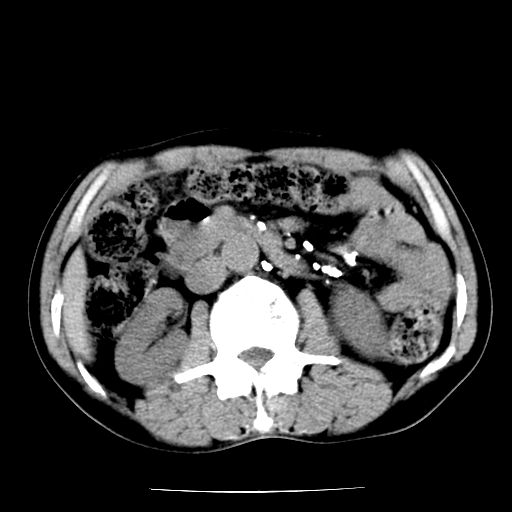

男,59岁,“结核性胸膜炎”30余年,胸部经常疼痛,多次x检查提示“肺部”炎症。腹部疼痛5日,b超提示:“肝内短管结石,余显示不清,建议进一步检查。”

两肺结核并右侧胸腔积液;脾脏、腹腔及腹膜后淋巴结结核[陈旧性];肝内胆管结石

胸部腹部都是结核(双肺。纵隔淋巴结,肝脏,脾脏,肠系膜)

两肺结核并右侧胸腔积液;脾脏、腹腔及腹膜后淋巴结结核[陈旧性];肝内胆管结石。直肠息肉?